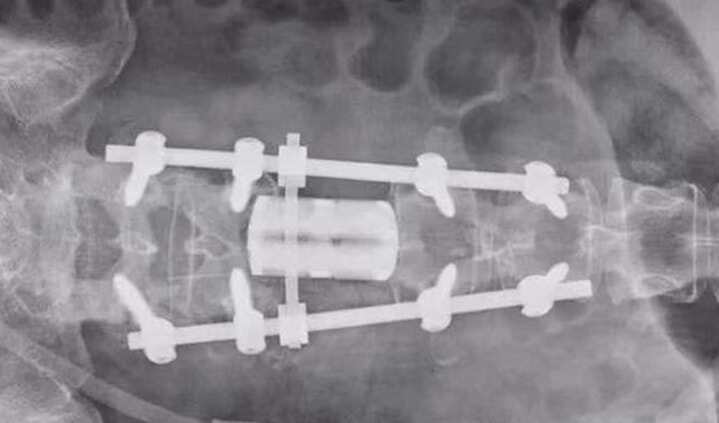

新疆醫(yī)科大學(xué)第三臨床醫(yī)學(xué)院完成3D打印人工椎體置換手術(shù)

行業(yè)資訊 1012天前

今日,據(jù)魔猴網(wǎng)了解,新疆醫(yī)科大學(xué)第三臨床醫(yī)學(xué)院(附屬腫瘤醫(yī)院)骨與軟組織腫瘤及黑色素瘤科聯(lián)合麻醉與圍術(shù)期醫(yī)學(xué)中心、輸血科等多個(gè)學(xué)科,成功完成新疆首例3D打印人工椎體置換手術(shù)